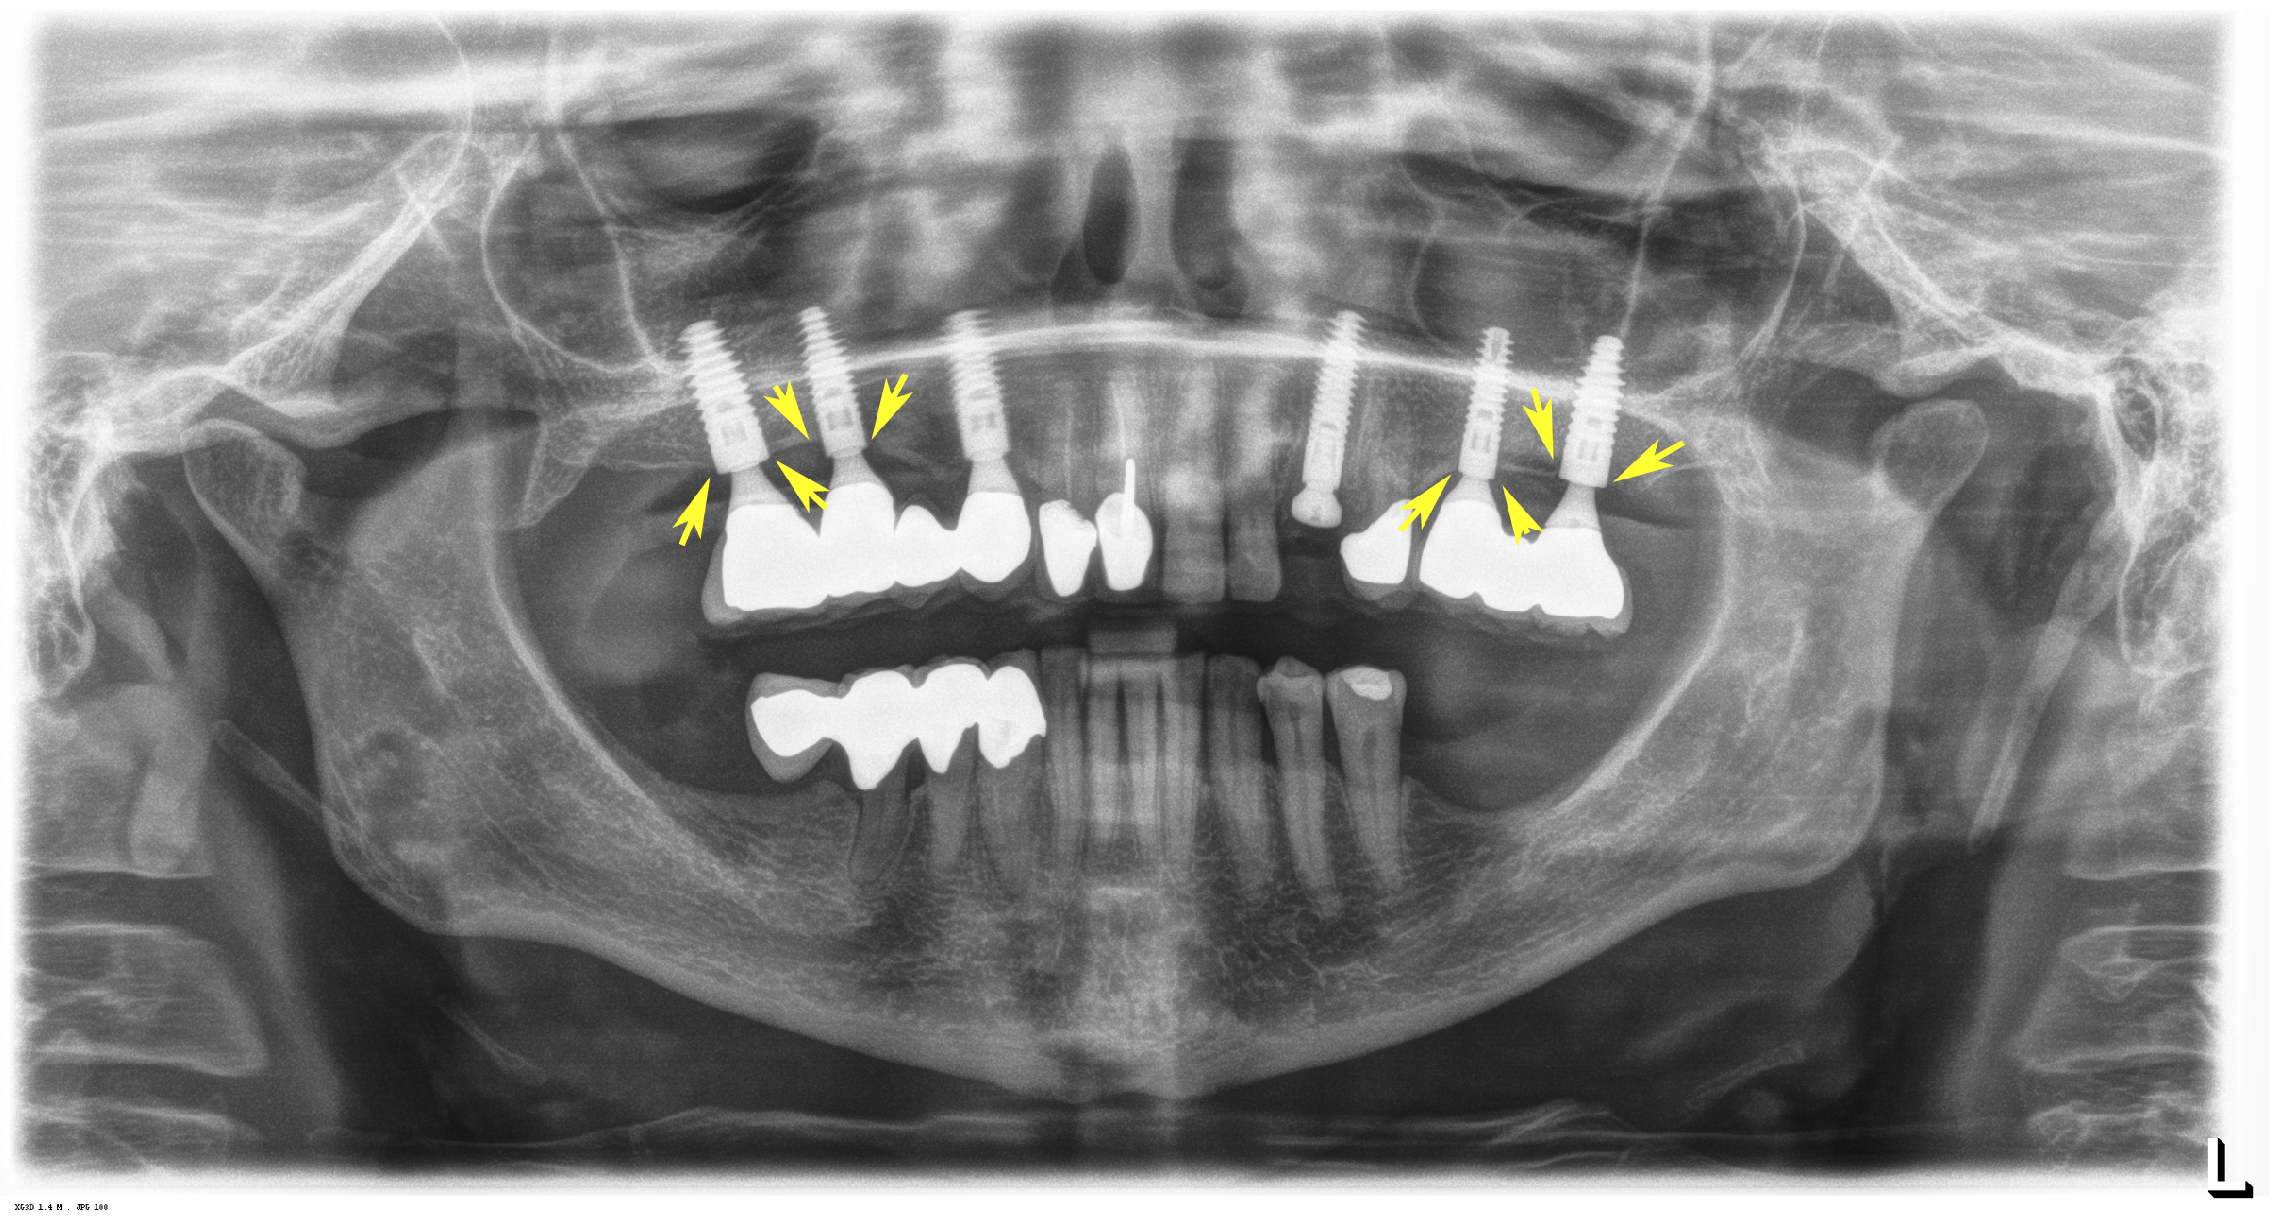

2.3.1. Cone Beam CT

2.3.2. Data Transfer, Analysis and Volume Determination

3.2. Radiological Results

3.4. Dental Implant Performance 6 Years after Placement